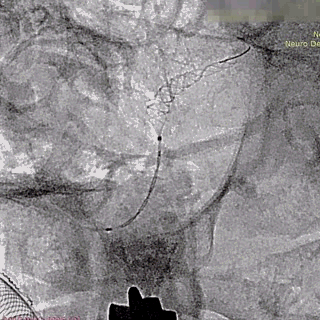

支架及支架微导管到位。

支架头端打开。

支架远端打开造影。

等张释放,支架中段打开至50%释放标记点。

支架中段打开造影。

支架近端打开,完全释放。

支架完全释放造影。

术后即刻造影。